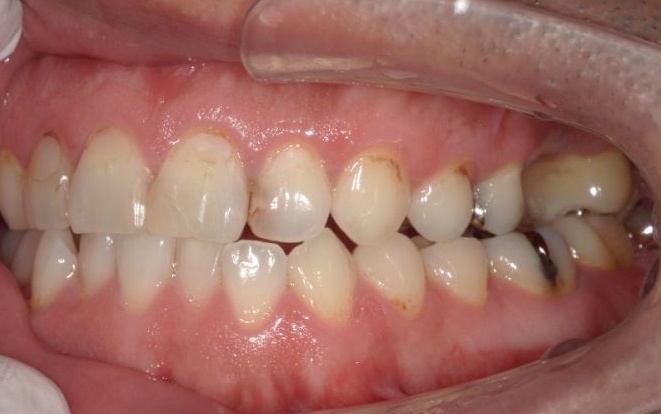

④上下左右の奥歯には、銀合金の古い詰め物「アマルガム」が装着されていました。今回は保険診療の範囲内で、CRと金属の詰め物「インレー」による修復を行い、全体的な噛み合わせと審美性を改善します。

次に、右上奥歯の古い材料(以前の根管治療に使用したもの)を除去し、歯根内部の洗浄と消毒をしてから新しい材料で密封し、被せ物を作製して装着しました。

最後に、古いアマルガムを除去した部分は保険診療の範囲で治療を行い、見た目や噛み合わせなどに問題がないことを確認して、治療を終了しています。